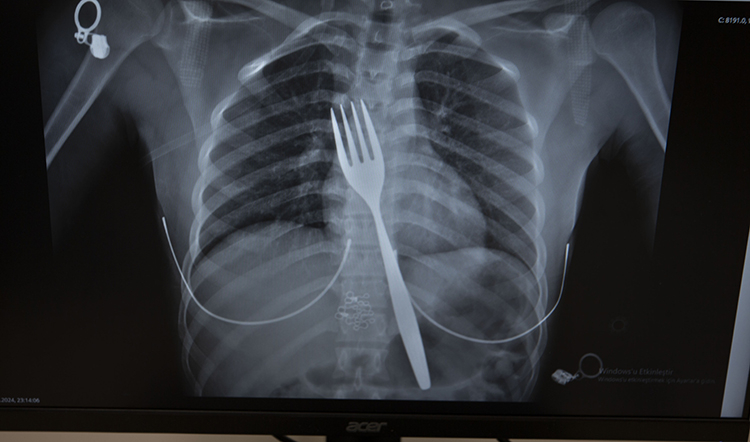

Söke'de yaşayan yabancı uyruklu E.E (18), yemek çatalı yuttuğu şikayetiyle ambulansla Aydın Adnan Menderes Üniversitesi (ADÜ) Hastanesine getirildi.

Burada röntgeni çekilen hastanın yemek borusunda 18 santimlik çatal olduğu tespit edildi.

Vakayı ilk duyduğunda şaşırdığını anlatan Edizsoy, "Büyük bir çatalın tamamen yutulması şeklinde ortaya çıkan bu vakayı ilk duyduğumda doğru olmadığını düşündüm. Hasta 18 yaşında ve yabancı uyrukluydu. Türkçesi biraz zayıf olduğu için belki de yanlış anlaşılmalar olabileceğini düşündük. Ama hastanın filmini çektiğimizde gerçekten bir çatalın yemek borusunda olduğunu gördük." dedi.